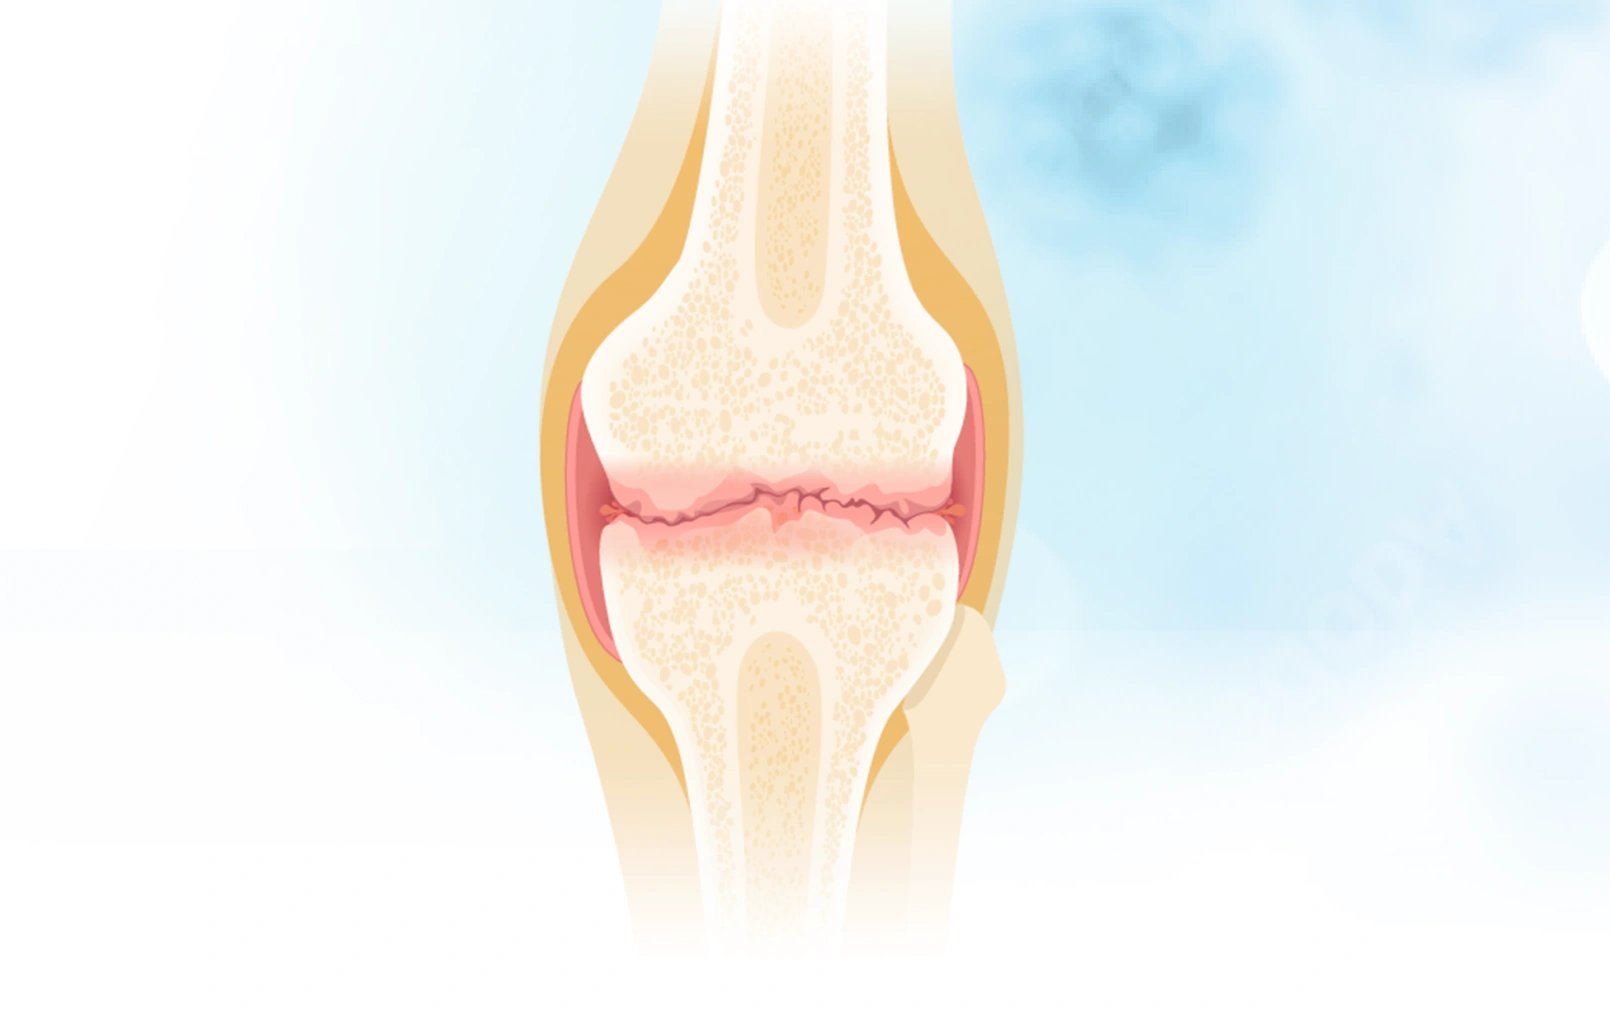

关节里的“减震器”去哪了?深度拆解骨关节炎的本质

骨关节炎不是一个突然降临的诅咒,而是长期“错误使用”身体的结果。 请记住: 软骨(减震垫)需要被温柔对待。 滑液(机油)需要通过科学运动来保持新鲜。 全...

骨关节炎的病理生理机制

你有没有想过,为什么有些人50岁就膝盖疼得上不了楼,而有些人80岁还能爬山? 为什么关节里那层看似不起眼的软骨一旦出问题,就能让一个人从"健步如飞"变成"举步...